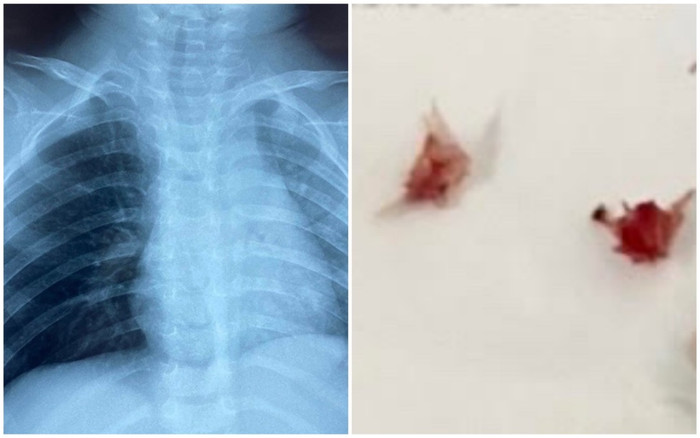

Qua thăm khám bác sĩ nghi ngờ có dị vật đường thở ở phổi phải và hình ảnh X quang ghi nhận tắc nghẽn ứ khí ở phế trường bên phải.